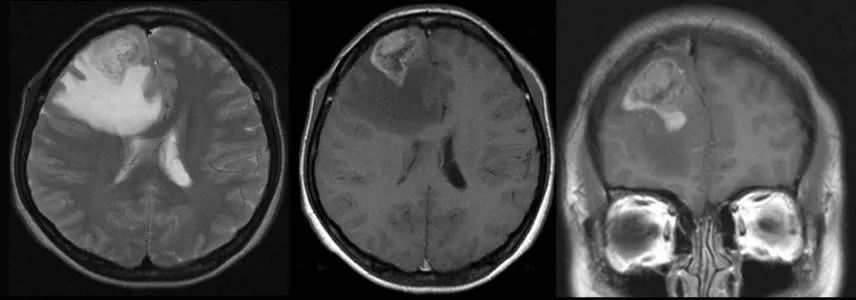

脑瘤一般有良恶性之分,良性脑瘤主要是指生长在颅内某一部位,组织分化良好,生长缓慢,多能根治肿瘤。如脑膜瘤、垂体腺瘤等。而恶性脑瘤则相反,细胞分化不良,生长迅速,难以根治。如脑内胶质瘤、转移瘤及侵进瘤等多为恶性。

良性脑瘤(WHO Grad 1 和Grad 2级)如脑膜瘤、听神经瘤、三叉神经器鞘瘤、垂体瘤等,通过手术全切即可治愈的效果,获得如同常人一样的生存期,很多Grad 2级脑肿瘤患者可达到术后10年、20年甚至30年不复发。

但有些良性脑瘤,由于位置较深,其四周有很多重要结构,而发现时由于体积已很大,手术不仅不能全部切除,而且预后不良。而某些所谓恶性脑瘤,由于生长在不很重要脑组织中,几乎能全部切除,手术后也能生存较长时间,甚至能治愈。有较个别脑瘤,开始为良性,以后逐渐转变成恶性。因此,不论患了何种性质脑瘤,都不应该掉以轻心,应及时到就诊。